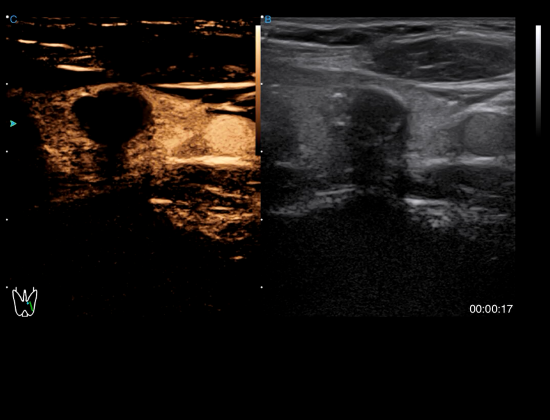

Contrast Harmonic Imaging

The blood flow perfusion status can be visualized in real time with contrast agent for efficient analysis of tumors in liver, thyroid and other organs. The timer function further enhances the diagnostic accuracy.